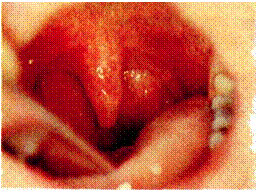

230. Острый флегмонозный ларин- 231. Флегмонозно-абсцедирующий гит. Отек черпаловидных хрящей ларингит. В задних отделах верхне-и черпалонадгортанных складок. го этажа гортани определяется

формирующийся абсцесс с выраженным перифокальным воспалением